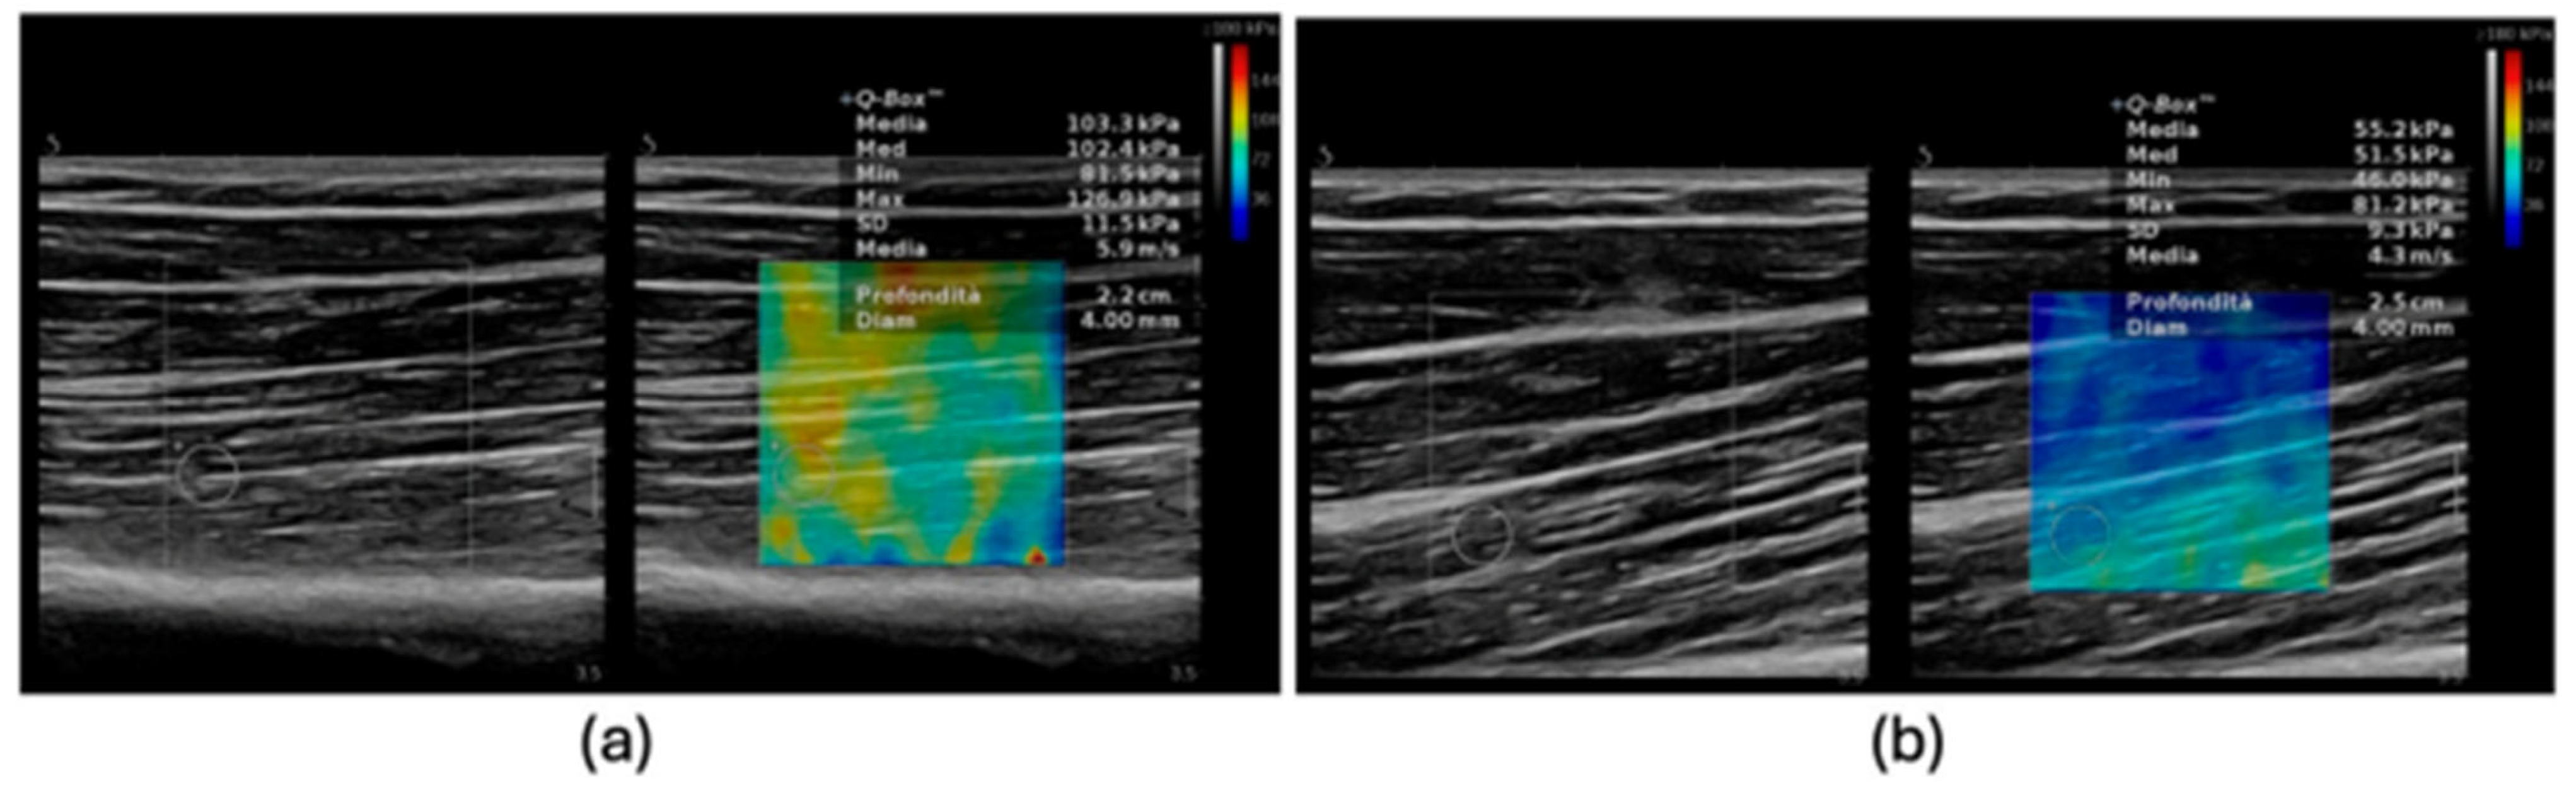

| Becchetti et al. (2023) [57] | Cirrhosis | Young’s modulus (kPa) | Aixplorer (Supersonic Imagine) | 3.5–5 MHz | Transverse/RF, VM, IP | Supine, rest 7 min | Relaxed | 3 per muscle |